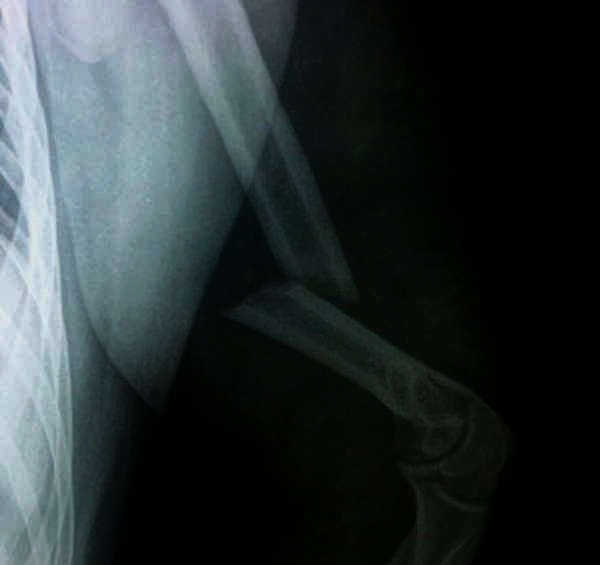

FRACTURE OF THE HUMERUS:

Radiographic image of a fracture of the humerus (COURTESY of W. Robert Strauss, Jr.) SEE: acromiohumeral; SEE: capitellum; SEE: cubitus; SEE: glenoid cavity

In a fracture of the shaft and lower end of the humerus, the limb is put in a cast in a position midway between pronation and supination with the humerus at right angles to the forearm. Movement of the shoulder, wrist, and finger is allowed.